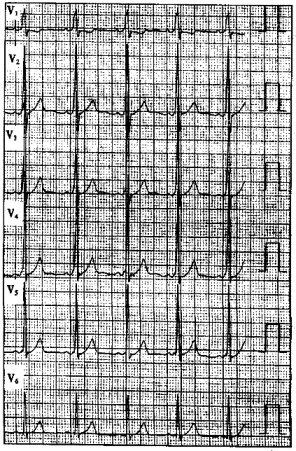

患者男性,40歲,多次發作心悸,心電圖一-見下圖,顯示為預激圖形。

正確答案:6.D;7.B;8.B;9.B 解題思路:食管心房調搏可以誘發心動過速并確定心動過速的發生機制。該心電圖顯示V。導聯delta波向上,旁路位于左側;Ⅱ、Ⅲ、aVF導聯delta波向上,提示旁路位于左側壁;當旁路前傳有效不應期<270ms或預激綜合征合并心房顫動時最短RR間距≤240ms時,提示為高危旁路;逆向型房室折返性心動過速的折返途徑為:心房→旁路→心室→房室結→心房。